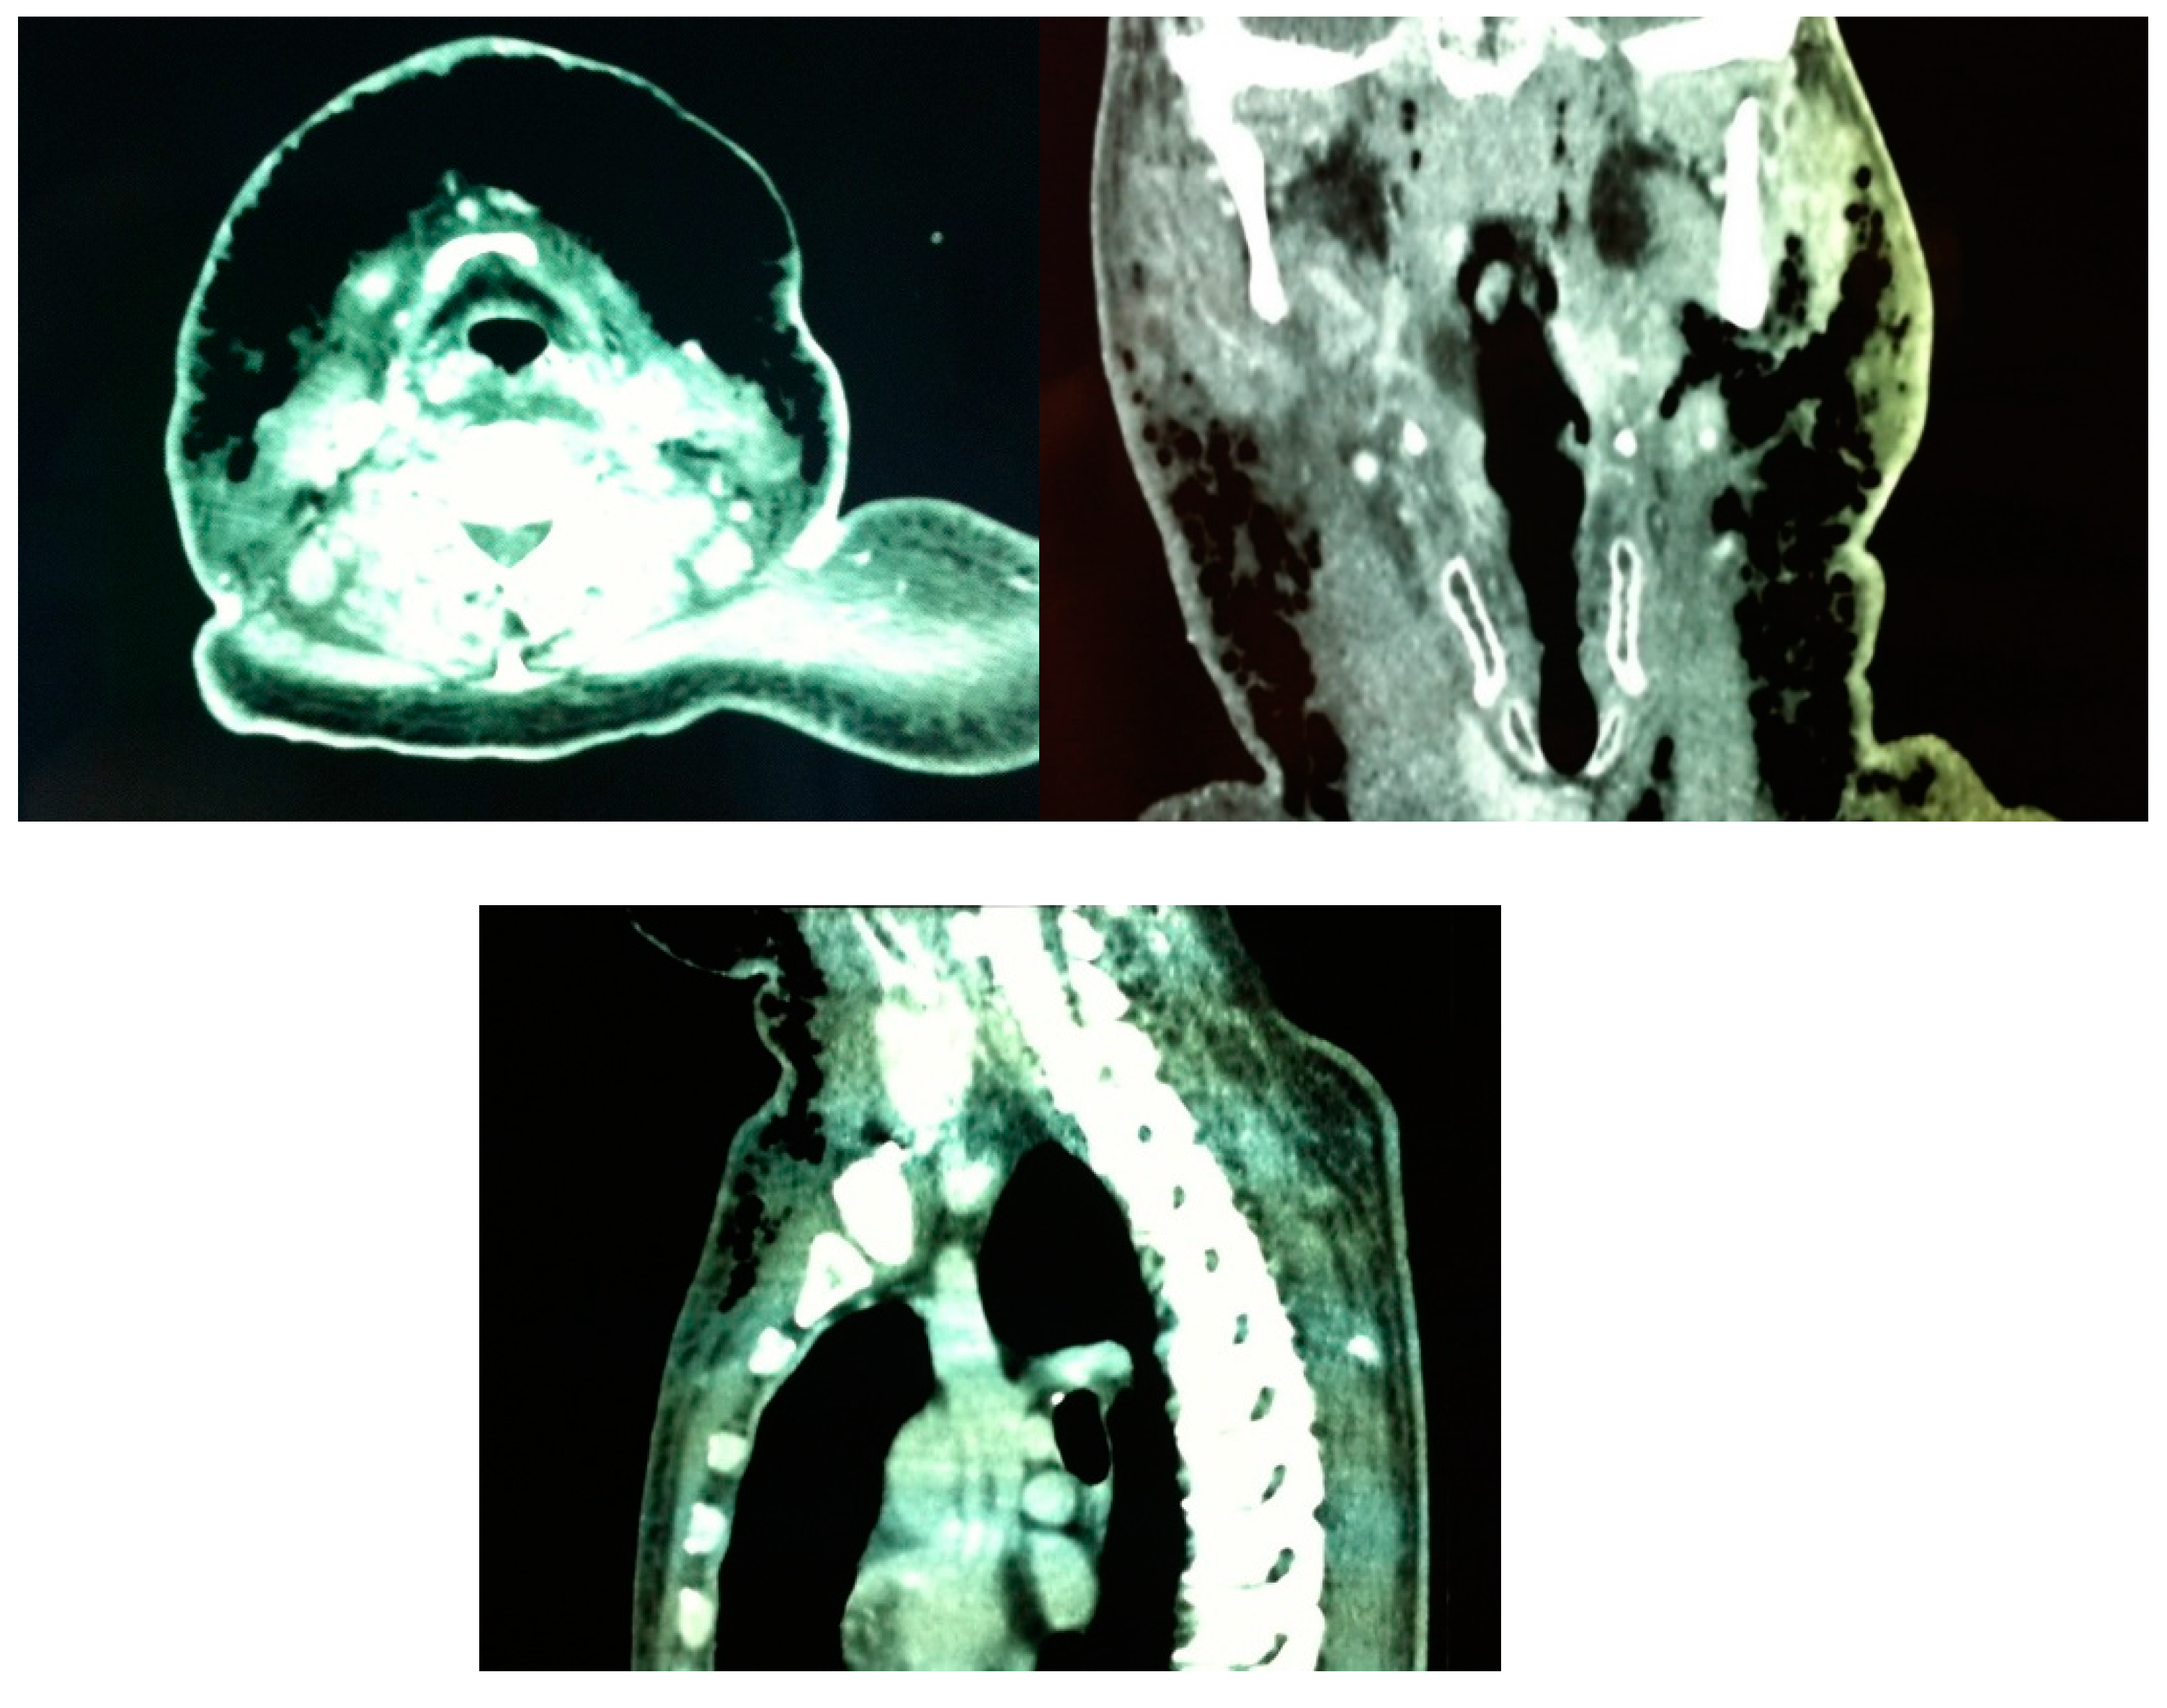

Figure 2.

Patient A. Preoperative CT scan showing abundant gas extending subcutaneously from the upper anterior chest wall and the anterolateral neck bilaterally up to the paramandibular region.

36] defined constant diagnostic features found on CT scans of patients with histologically confirmed NF: 1) cellulitis (diffuse thickening of cutaneous and subcutaneous tissue and reticular enhancement of the subcutaneous fat); 2) fasciitis (thickening and/or enhancement of cervical fascia); 3) myositis (asymmetric thickening or enhancement of cervical muscles) and 4) fluid collections in multiple neck spaces. Gas collections and involvement of the mediastinum were inconstant findings. Involvement of the superficial cervical fascia and thickening and/or enhancement of sternocleidomastoid muscle were present in all patients. CT scan of our first patient showed abundant and continuous gas collections, descending from the mandibular region to the upper portion of the anterior thoracic wall (

Figure 2), in contrast with Becker et al.[

36] findings where all gas collections were located within fluid collections.